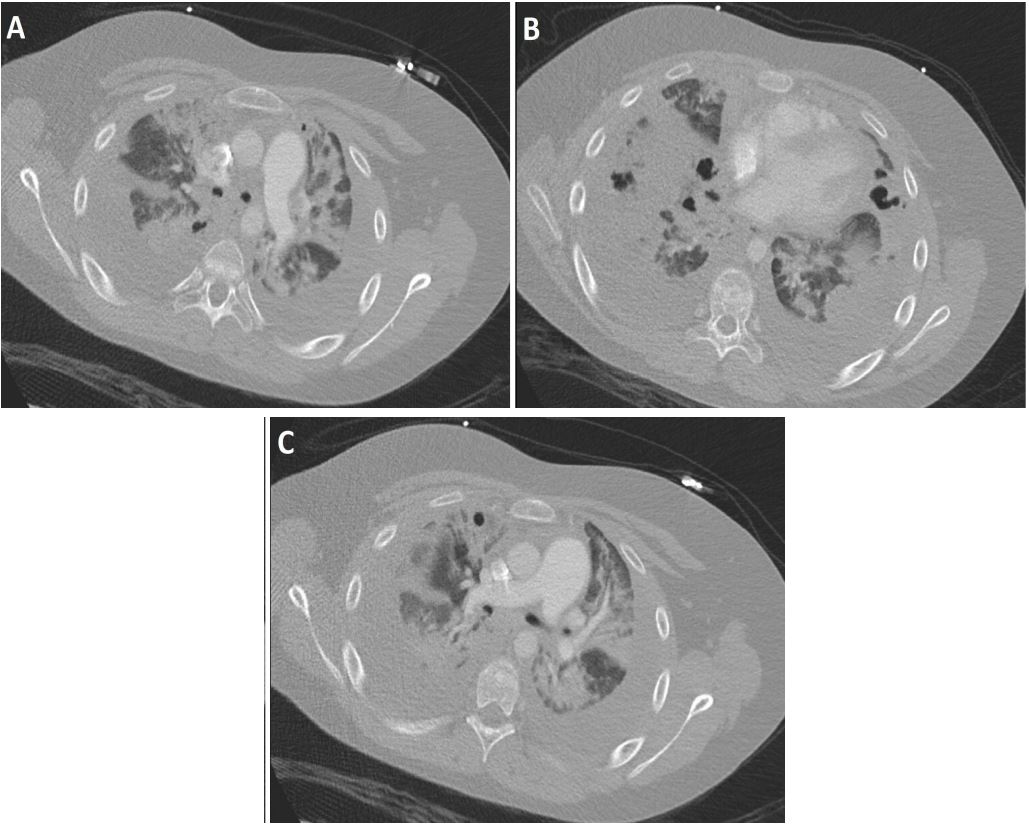

An early adolescent, overweight boy with a history of foetal alcohol syndrome presented with respiratory insufficiency due to COVID-19 pneumonia (Figure 1A for typical ground glass opacities on CT-scan). Prior to this infection, he had not received any vaccine against COVID-19, did not have a history of fungal infections and had not been in contact with tuberculosis to our knowledge. Because of severe tachydyspnea and an O2 saturation of 80%, despite being treated with Continuous Positive Airway Pressure (CPAP), he was intubated and transferred, in prone position, to our Pediatric Intensive Care Unit (PICU) for respiratory support. Laboratory investigations were notable for pCO2 of 6.5 kPa, CRP 105 mg/L and D-dimer level of 35000 mcg/L. He was treated with dexamethasone, ceftriaxone and a single dose of tocilizumab according to adult guidelines at that time as he was in need of respiratory support and therefor in critical condition [1]. His clinical course was complicated by pulmonary embolisms for which he was treated with Low Molecular Weight Heparins (LMWH). The D-dimer level at that time was >10000 mcg/L (Figure 1B for bilateral segmental pulmonary embolisms).

Figure 1: (A,B) CT scan at time of admittance.